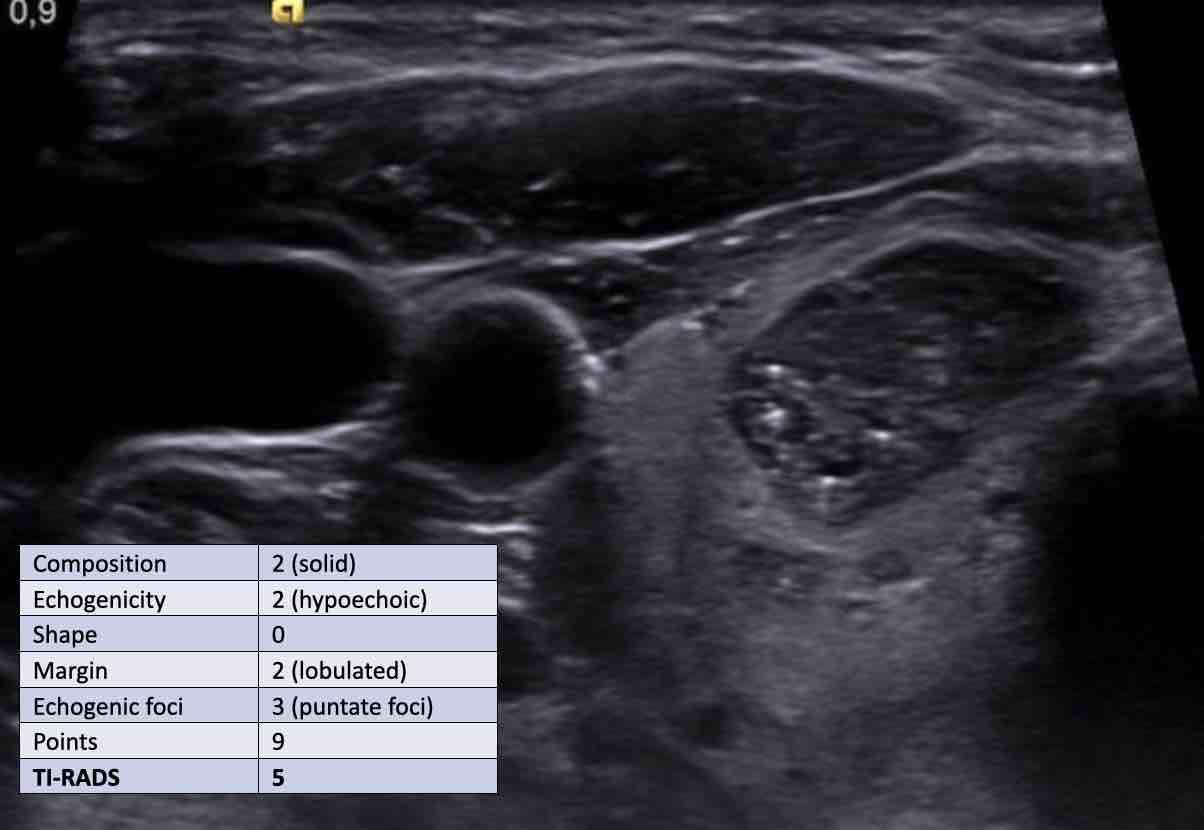

Ca 2

Xem hình ảnh và xác định điểm TI-RADS.

Cuộn hình ảnh để xem điểm TI-RADS.

Tiến hành phân tích bên dưới.

Điểm TI-RADS: 1 điểm cho sự hiện diện của vôi hóa thô.

Tổn thương này được phân loại TI-RADS 5, chủ yếu do tính chất giảm âm rõ rệt.

Nếu tổn thương có chiều cao lớn hơn chiều rộng, điều này sẽ cộng thêm 3 điểm.